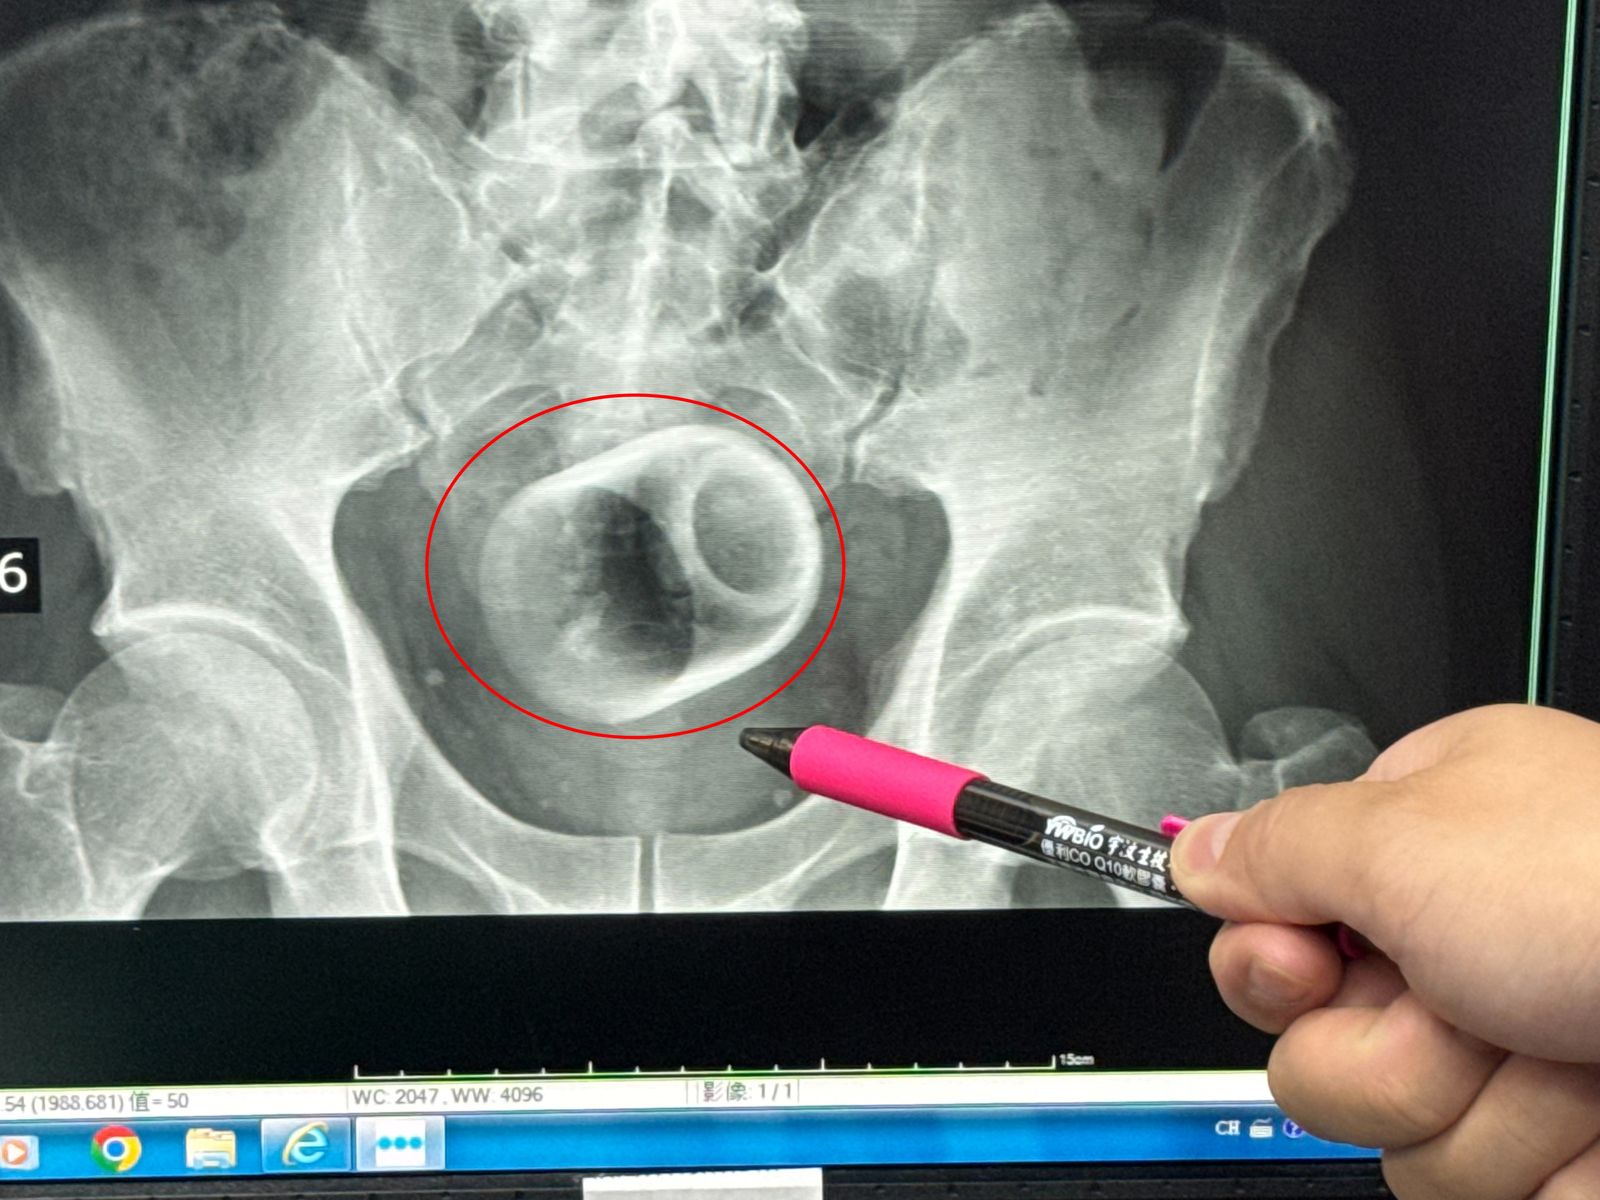

男子3天無法排便!醫檢查大驚:菊花裡...